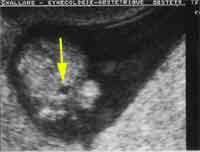

12 semaines